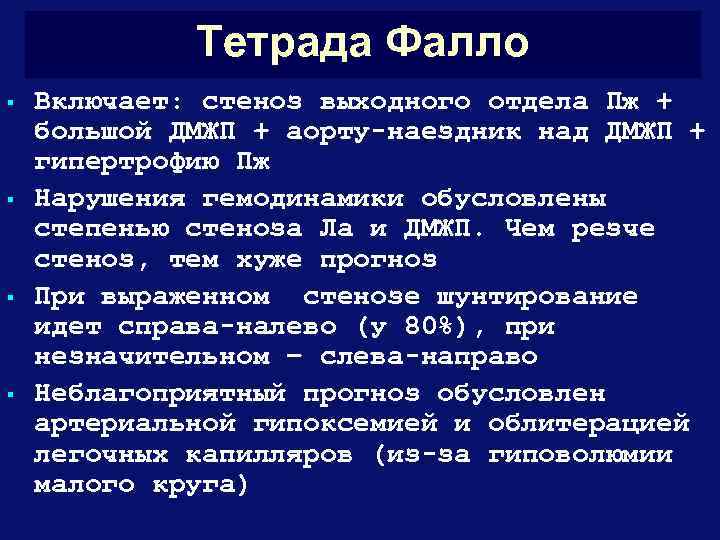

Тетрада Фалло § § Включает: стеноз выходного отдела Пж + большой ДМЖП + аорту-наездник над ДМЖП + гипертрофию Пж Нарушения гемодинамики обусловлены степенью стеноза Ла и ДМЖП. Чем резче стеноз, тем хуже прогноз При выраженном стенозе шунтирование идет справа-налево (у 80%), при незначительном – слева-направо Неблагоприятный прогноз обусловлен артериальной гипоксемией и облитерацией легочных капилляров (из-за гиповолюмии малого круга)